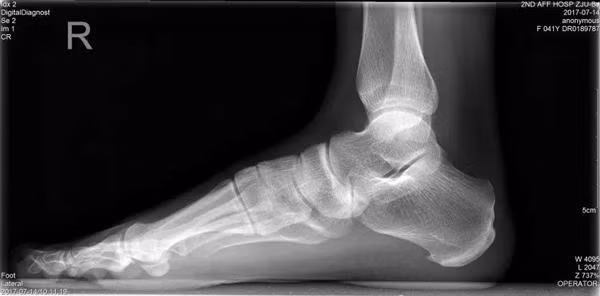

Cô Lí, nay 54 tuổi từng là giáo viên dạy tiếng Anh tại trường trung học. Từ khi còn nhỏ cô đã có một “bàn chân bẹt” – tức là gan bàn chân phẳng lì, không có vết lõm vòng cung như mọi người.

Dù đã tới nhiều bệnh viện để kiểm tra và điều trị nhưng cơn đau của cô Lí vẫn không thuyên giảm, cho tới khi cô gặp được bác sĩ Miêu Húc Đông. Bác sĩ Miêu đã tiến hành kiểm tra bàn chân cô Lí và phát hiện cô bị “hội chứng bàn chân bẹt” vì thường xuyên đứng lâu, đi giày cao gót.

Bàn chân bẹt, gan chân phẳng lì là một dạng dị tật phổ biến trên thế giới, gây ảnh hưởng nghiêm trọng đến thần kinh cột sống.

Tất cả trẻ sơ sinh đều có bàn chân không có vòm, hay còn gọi là bàn chân bẹt. Khi trẻ đến độ tuổi từ 2 đến 3, vòm bàn chân được hình thành. Cùng với hệ thống dây chằng, vòm bàn chân giúp cho chúng ta có thể chịu lực, cân bằng, đi đứng nhẹ nhàng, giúp giảm phản lực từ mặt đất dội lên khi chân di chuyển. Thông thường, những ai có hệ thống dây chằng quá lỏng lẻo sẽ dễ bị bàn chân bẹt. Đó là vì các xương ở bàn chân không được cố định tốt.

Bàn chân bình thường.

Bàn chân bẹt.